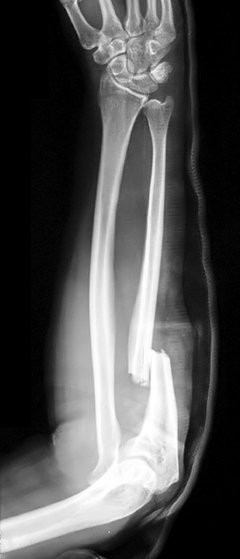

Osteoporosis paling sering terjadi pada tulang pinggul, tulang belakang, dan pergelangan tangan. Tulang terdiri dari sel-sel yang rutin diganti. Penyakit osteoporosis terjadi ketika proses penyusunan sel tulang baru tidak seimbang dengan sel tulang lama yang hilang. Osteoporosis dapat terjadi pada pria dan wanita dari seluruh ras dan etnis.

• Patah tulang secara tiba-tiba tanpa riwayat cedera.

• Sering mengalami patah atau keretakan tulang.

Kemudian dokter akan melakukan pemeriksaan penunjang untuk memeriksa apakah ada tulang yang patah. Pemeriksaan penunjang dapat berupa:

• Rontgen, CT scan atau MRI untuk melihat pencitraan area tulang atau jaringan-jaringan di sekitarnya.

Komplikasi dari osteoporosis yang cukup serius adalah patah tulang, terutama pada bagian tulang belakang dan tulang pinggul. Patah tulang pinggul paling sering disebabkan karena insiden terjatuh. Patah tulang bisa menyebabkan disabilitas permanen serta kematian dalam satu tahun pertama setelah cedera.

Sementara itu, patah tulang belakang dapat terjadi tanpa adanya insiden terjatuh. Tulang yang menyusun tulang belakang dapat melemah dengan sendirinya akibat massa jenis tulang yang menurun drastis dan merubah postur tubuh.